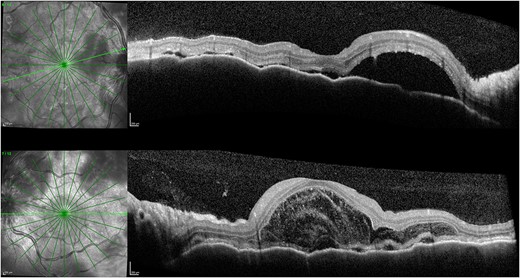

One week after initial review, the patient presented with eye casualty with deteriorated vision of 6/9 in the right eye and count fingers in the left eye. Intraocular pressure was within normal limits in both eyes. Anterior segment examination showed mild anterior uveitis with mild conjunctival injection, 1+ cells in the right eye, 2+ cells in the left eye, and 0.5+ cells in the anterior vitreous of both eyes. No keratic precipitants or posterior synechiae were present in either eye. Fundoscopy revealed bilateral hyperemic discs and 360° choroidal detachments with serous retinal detachment involving the maculae (Fig. 1). There was no evidence of vitritis or retinitis. OCT illustrated detachments of the neurosensory retina and bacillary layers (Fig. 2). Fundus fluorescein angiogram (FFA) demonstrated bilateral disk hyperfluorecence, macular hyperfluorescent pinpoints, and no evidence of retinal vasculitis or ischemia (Fig. 3).

Right (A) and left (B) fundus examination illustrating hyperemic discs and circumferential choroidal detachments 1 week post initial presentation.